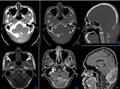

• 肾上腺嗜铬细胞瘤影像学表现韩毅力 / 副主任医师